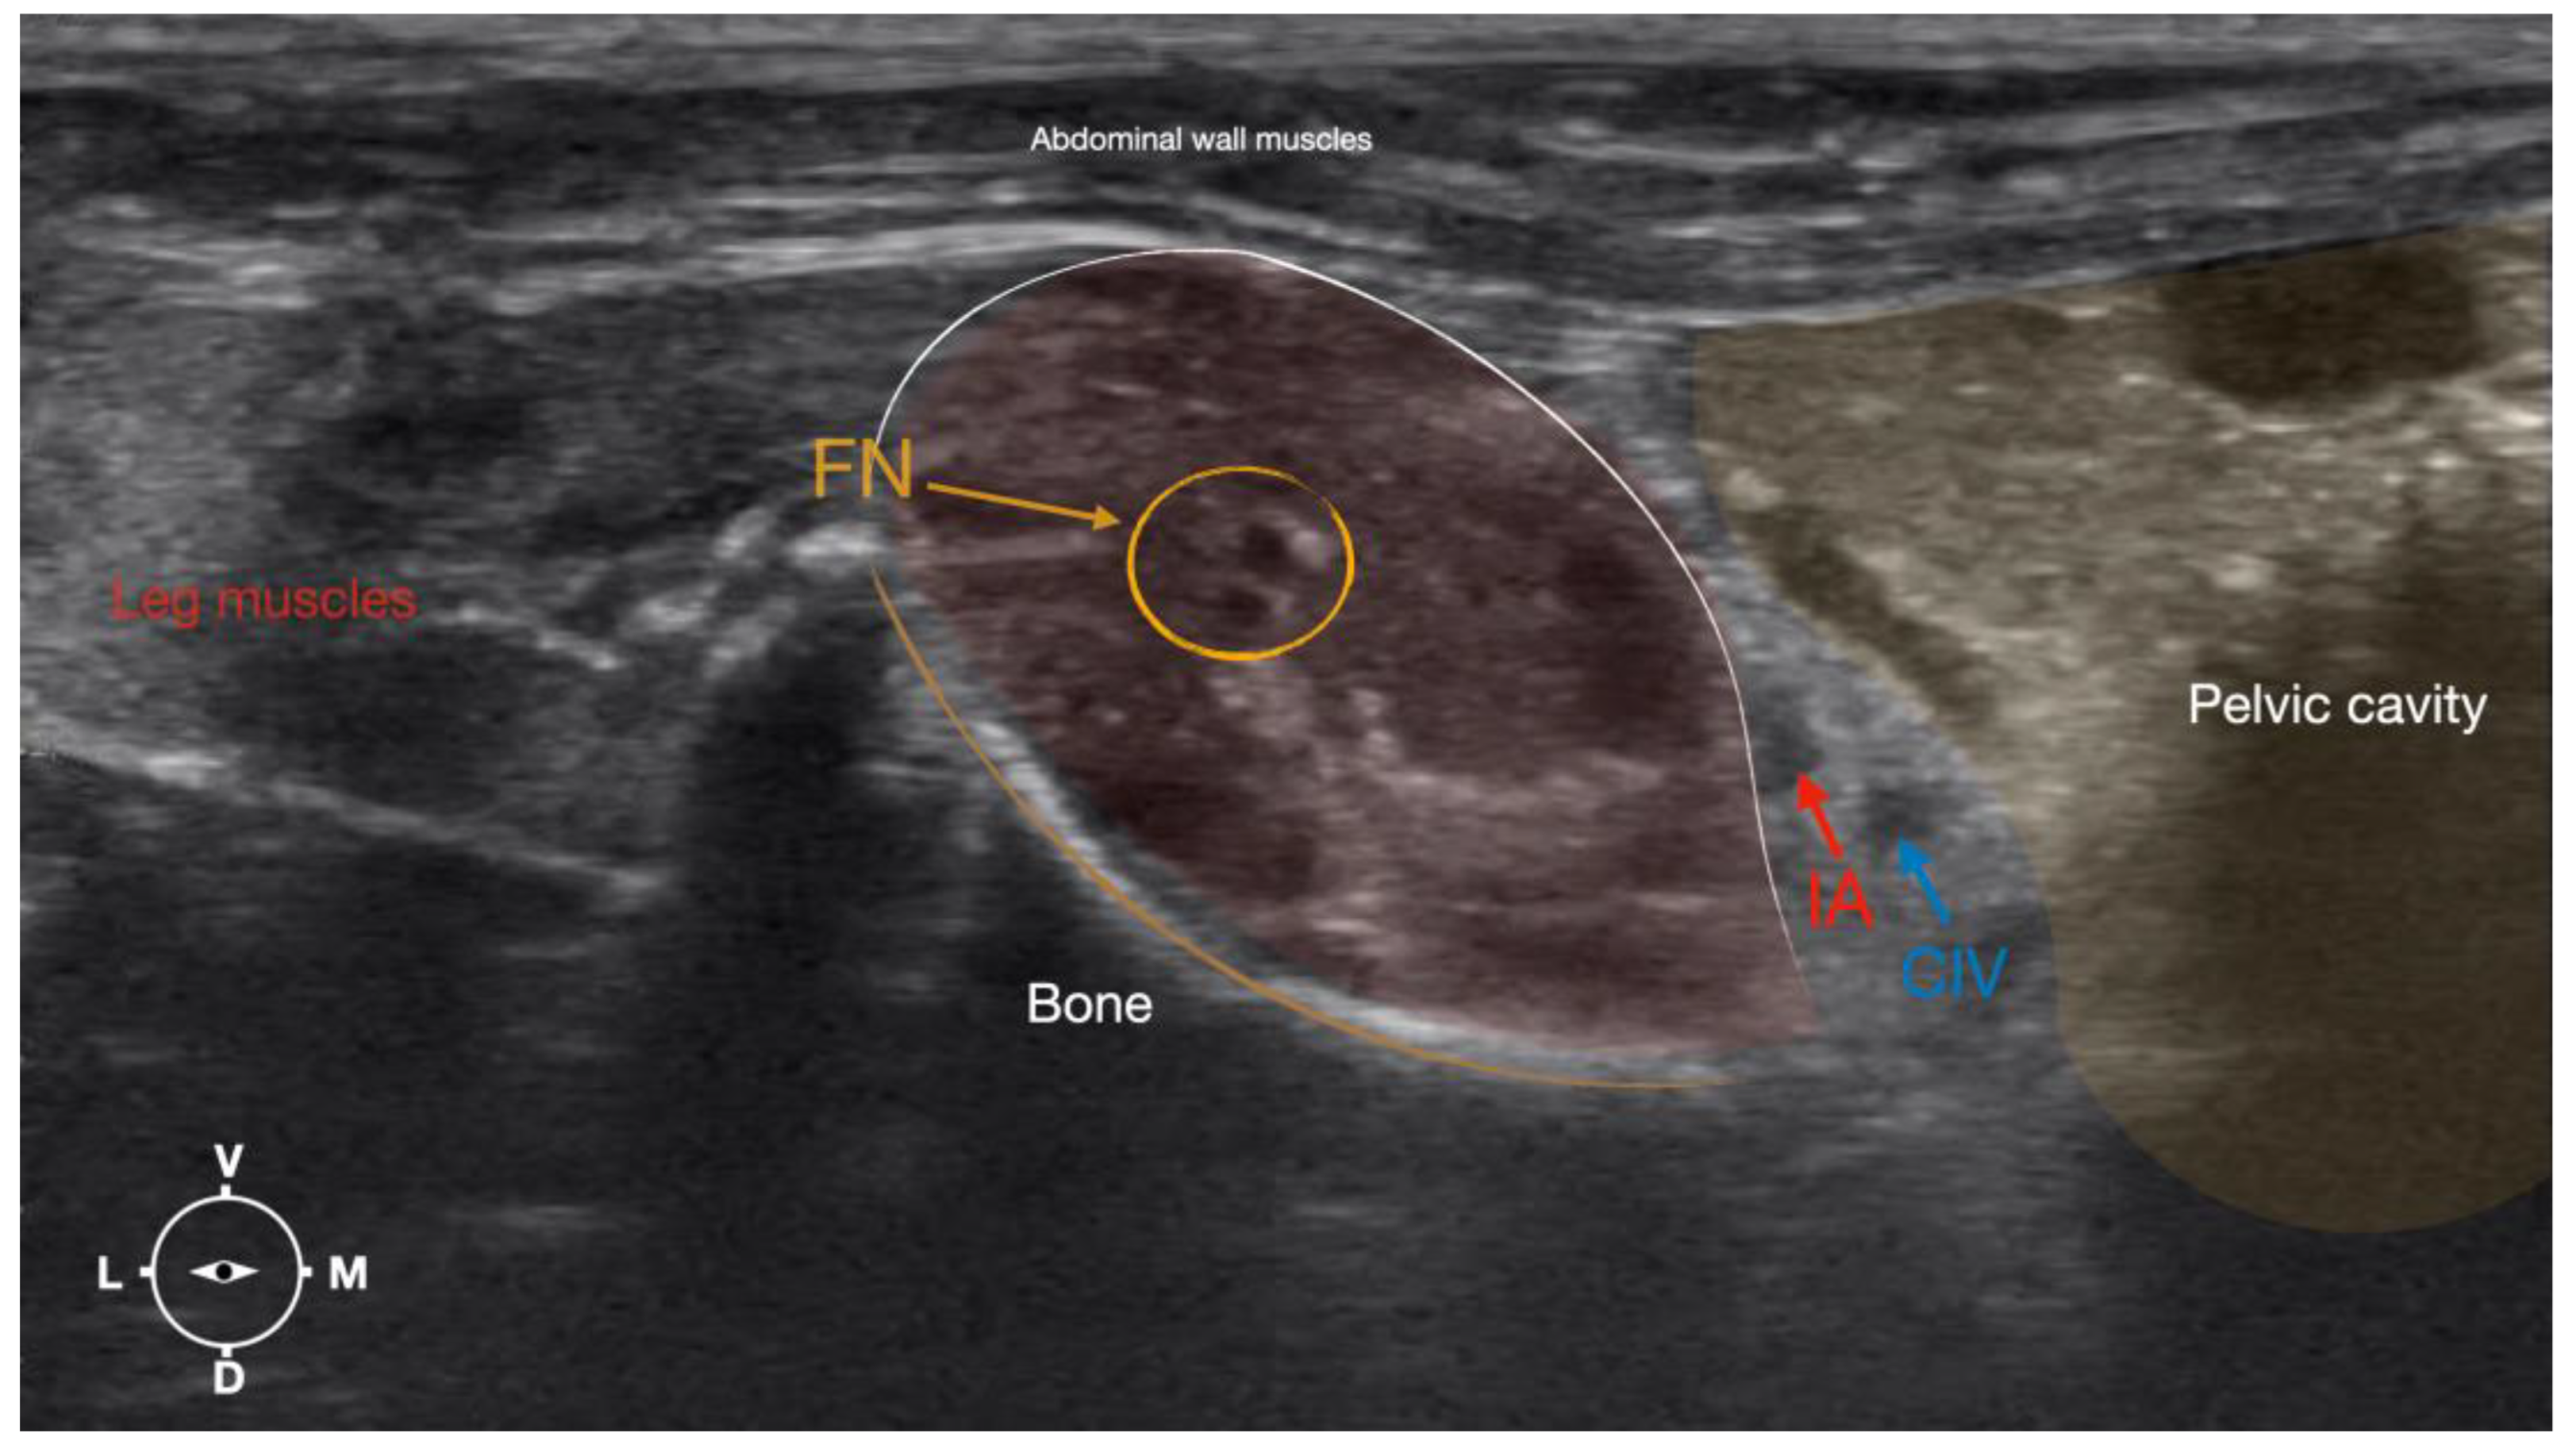

2.3.2. Femoral Nerve Injection

The cadaver was positioned in dorsal recumbency before the leg was extended caudally. The transducer was placed over the hypaxial muscles, transverse to the long axis of the spine, and at the level of the projection of the iliac crest. The window of interest was set at a depth of 2 cm to optimize the image. Then, the transducer was moved in caudal direction along the IPM until the femoral nerve was clearly seen in the substance of the IPM (Figure 4). A 50 mm 22-gauge insulated needle (Sonoplex Stim Cannula, Pajunk Medical Produkte GmbH, Germany) prefilled with a L-NMB solution was inserted using an in-plane approach. The needle was inserted at the lateral edge of the transducer and advanced in-plane under sonographic guidance through the iliac fascia and IPM in a dorso-medial direction towards the femoral nerve (Figure 5 and Figure 6). The needle was advanced until its tip was located in vicinity of the femoral nerve. A test volume of 0.05 mL of L-NMB was injected to confirm adequate distribution. The remaining volume of 0.15 mL/kg was then injected extraepineurally around the femoral nerve.

3.1.2. Femoral Nerve

The femoral nerve was found in the substance of the IPM with a dorso-ventral trace (Figure 8). It was divided into branches before it left the substance of the IPM to enter the leg through the vascular and muscular lacuna.

Based on the anatomical dissection and the US scans performed in this phase, the best way to locate and inject the FN was achieved by scanning the IPM from the projection of the iliac crest in the caudal direction. Ultrasonographically, the femoral nerve appeared as a hypoechoic structure in the dorsal part of the IPM, becoming hyperechoic/honey-comb-like in the ventral part of the mentioned muscle. The IPM was displayed as structures with heterogeneous echogenicity. The ilium and the vertebrae were displayed as a hyperechoic structure with acoustic shadow and located lateral and dorsal to the femoral nerve, respectively.

Figure 4. Corresponding transverse ultrasound image to Figure 5. The window of interest was set at a depth of 2 cm and the focus was at the level of the femoral nerve to optimize the image quality. The ultrasound image shows the FN and related structures. IA, iliac artery, CIV, common iliac vein; FN, femoral nerve; D, dorsal; L, lateral; M, medial; V, ventral.

Figure 6. Ultrasonographic image demonstrating the approach of the needle towards the femoral nerve. The window of interest was set at a depth of 2 cm and the focus was at the level of the femoral nerve to optimize the image quality. IA, iliac artery, CIV, common iliac vein; FN, femoral nerve; D, dorsal; L, lateral; M, medial; V, ventral.